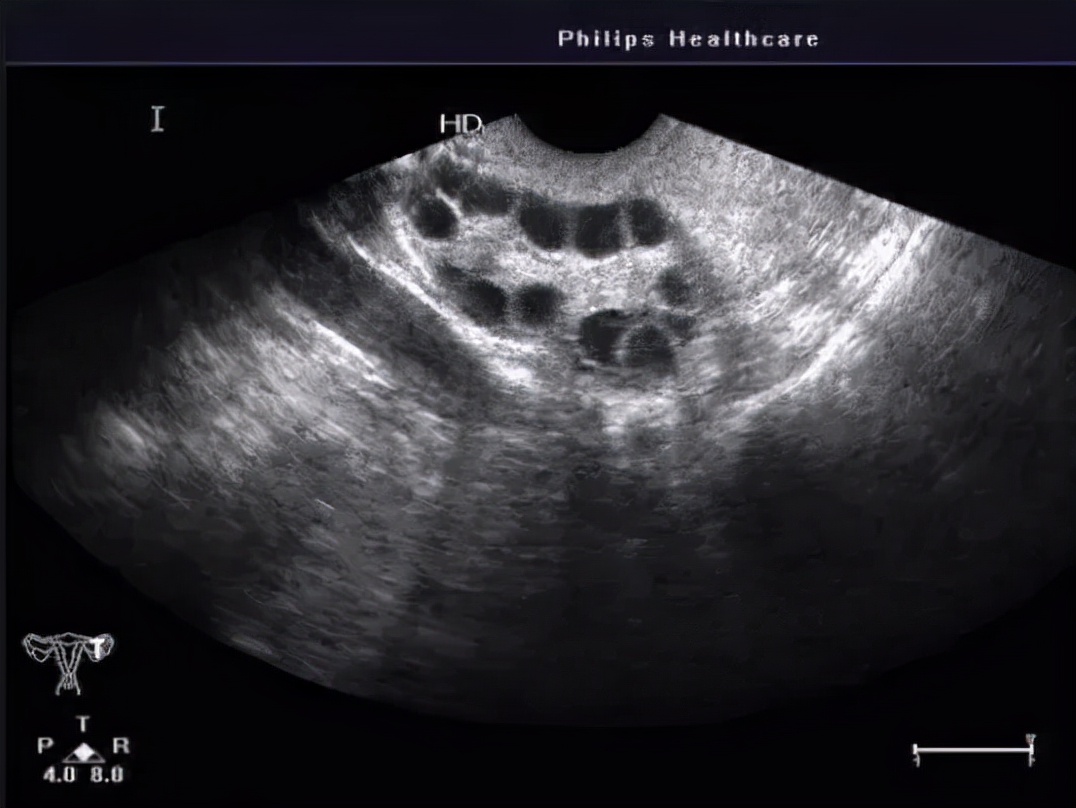

单侧或双侧卵巢呈现多囊性改变,即沿着卵巢外周有10个左右均匀的卵泡,俗称“项链征”,详见“ 月经不正常-多囊卵巢综合征 ”。这类囊肿还是很好鉴别的,需要结合月经情况、雄激素水平综合诊断及药物治疗,无需手术。